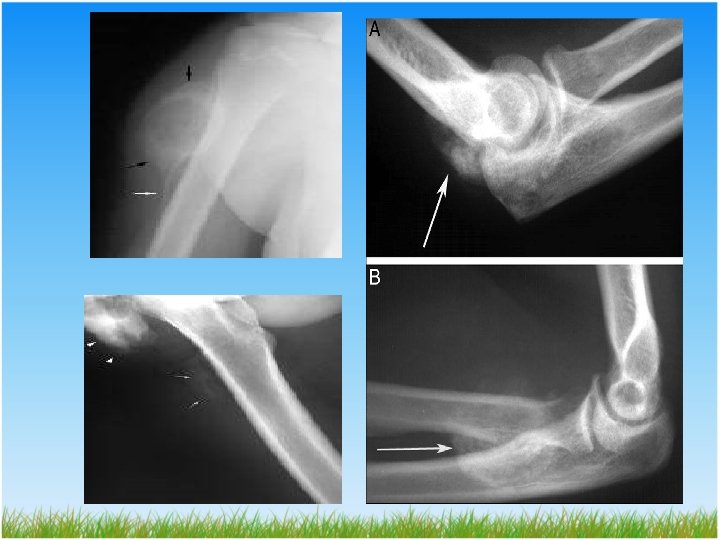

Hemiplejide HO • Hemiplejik olguların % 0. 5 -1. 2 bildirilmiş. • Sıklıkla omuz, dirsek ve kalça eklemlerinde • Risk faktörleri; – Spastisite – Rehabilitasyon sürecinin gecikmesi ve immobilizasyon – Mikro travma

Yanık Sonrası Gelişen HO • Görülme sıklığı %0. 2 -4 arasında değişmekte 1 • En sık dirsek eklemi posterioru tutulur • Uzun süreli immobilizasyon • Yanığın derecesi • Sistemik metabolik değişiklikler

TANI • Ultrasonografi; – Erken tanıda – İkinci haftadan itibaren kalsifikasyonlar oluşmaya başladığında • Santral zonda; Farklılaşmamış hücreler • İkinci zonda; Yumuşak osteoid • Periferal zonda; Osteoid ve kemik – Ayırıcı tanıda; DVT - abse - kas yırtığı - tümör